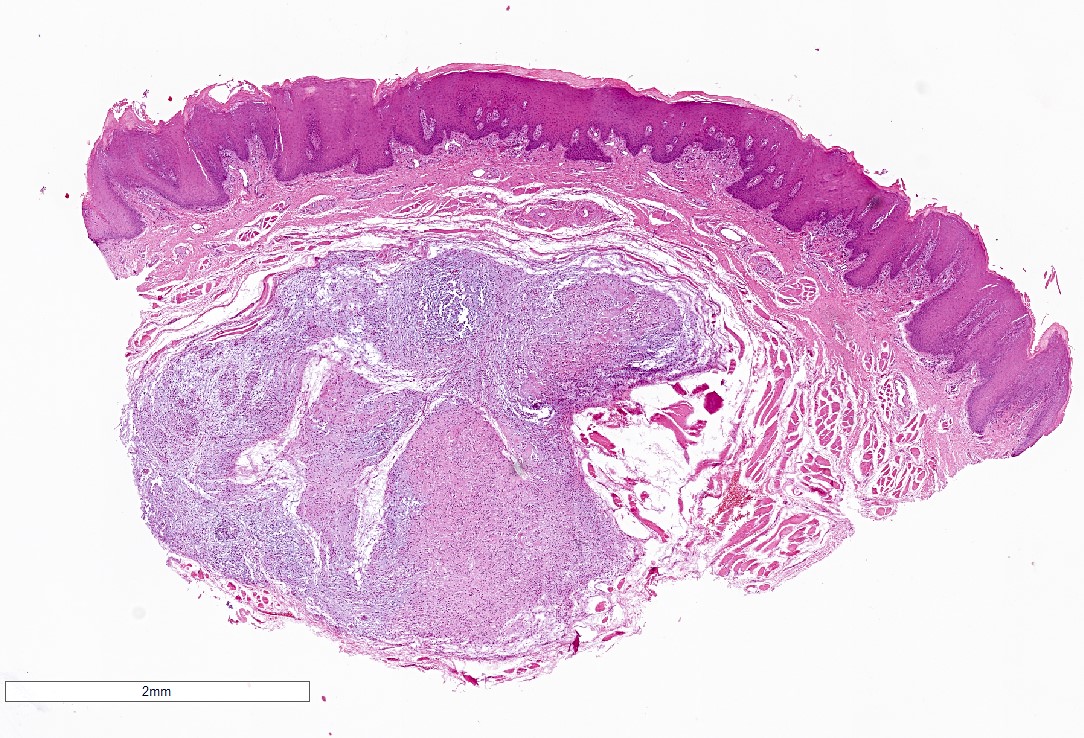

Microscopic (histologic) description

- Well demarcated tumor, often entrapped within skeletal muscle and frequently multilobulated (Am J Surg Pathol 2018;42:1297, Head Neck Pathol 2015;9:315)

- Stromal background may be hyalinized or demonstrate mucoid, myxoid or chondromyxoid areas

- Cords, strands or sheets of oval, round, fusiform or polygonal bland cells, sometimes arranged in a reticular / net-like or globoid pattern (Am J Surg Pathol 2018;42:1297)

- Myxoglobulosis-like changes have been noted (Virchows Arch 2003;442:302)

- May focally demonstrate fine calcifications, cellular atypia, necrosis, multinucleated giant cells (Am J Surg Pathol 2018;42:1297, Head Neck Pathol 2015;9:315, Oral Surg Oral Med Oral Pathol Oral Radiol Endod 1996;82:417)

- Cystic, slit-like spaces or hemorrhagic areas often noted (Head Neck Pathol 2014;8:329)

- Mitotic figures not seen (Head Neck Pathol 2015;9:315)

Microscopic (histologic) images